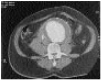

Fig. 2. Tomografía axial computarizada abdominal con contraste, donde se observa aneurima abdominal infrarrenal con trombo mural concéntrico y rotura con sangrado activo.